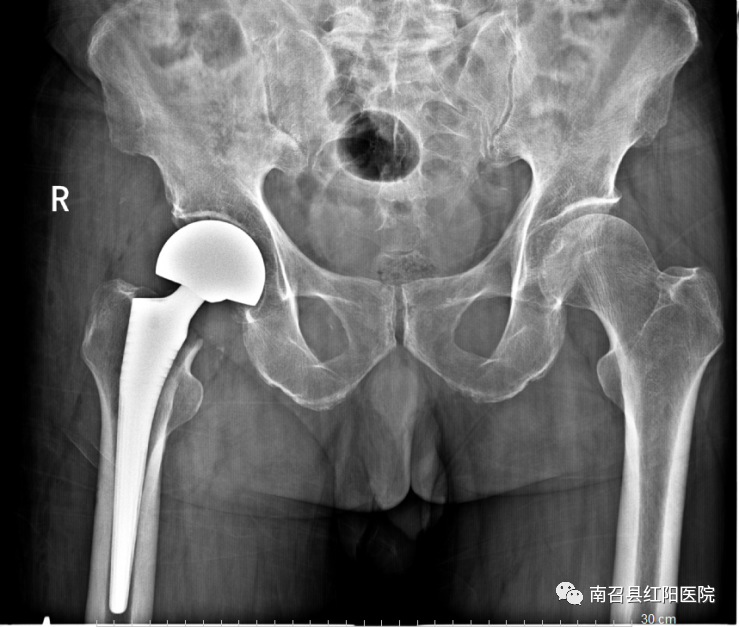

另一老年男性,孤寡老人,在养老院走楼梯时不慎摔倒,致股骨颈骨折,家中无人照顾,养老院请专门护工护理,与患者及其亲属商议后拟行手术治疗,手术顺利,术后恢复良好,术后3天即可拄拐下床活动,现患者已好转出院。